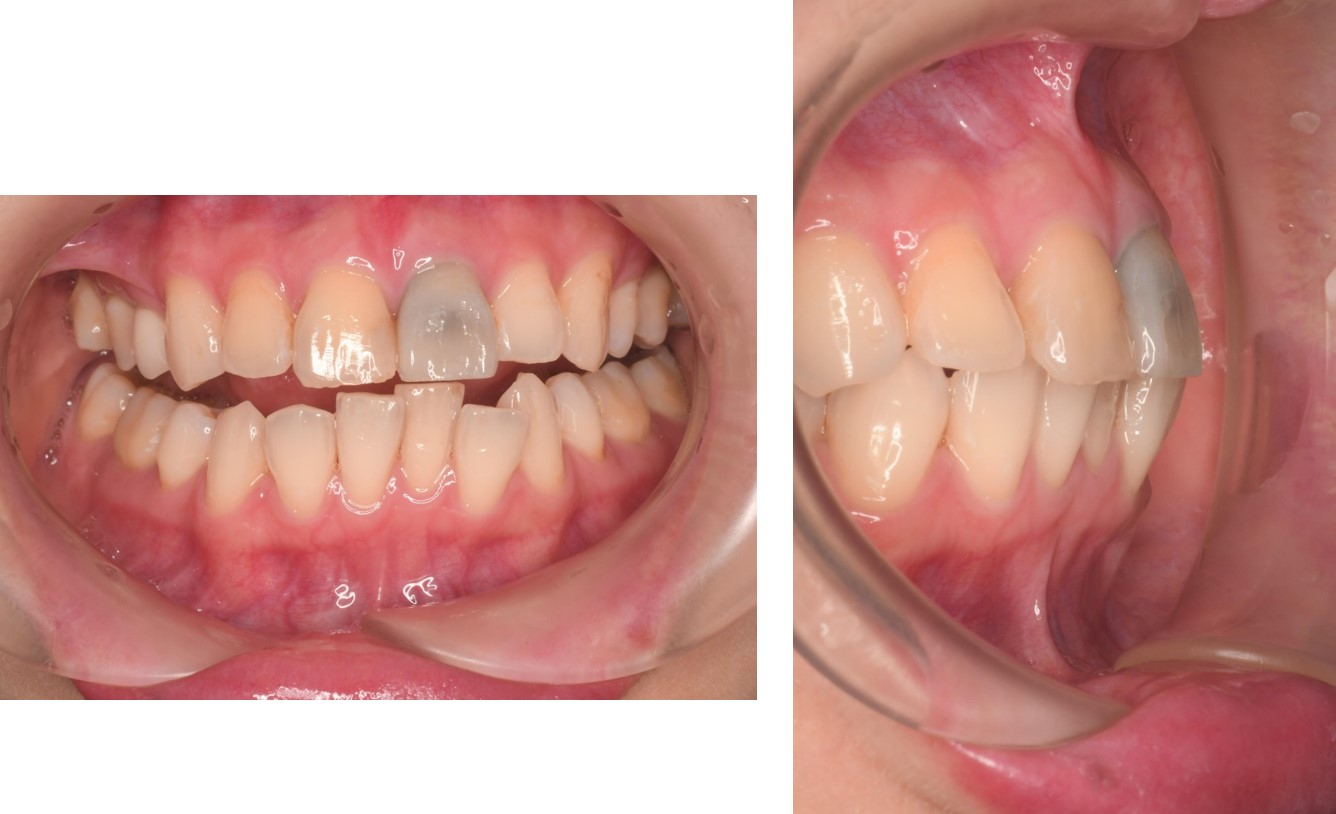

先更換上顎門牙臨時假牙